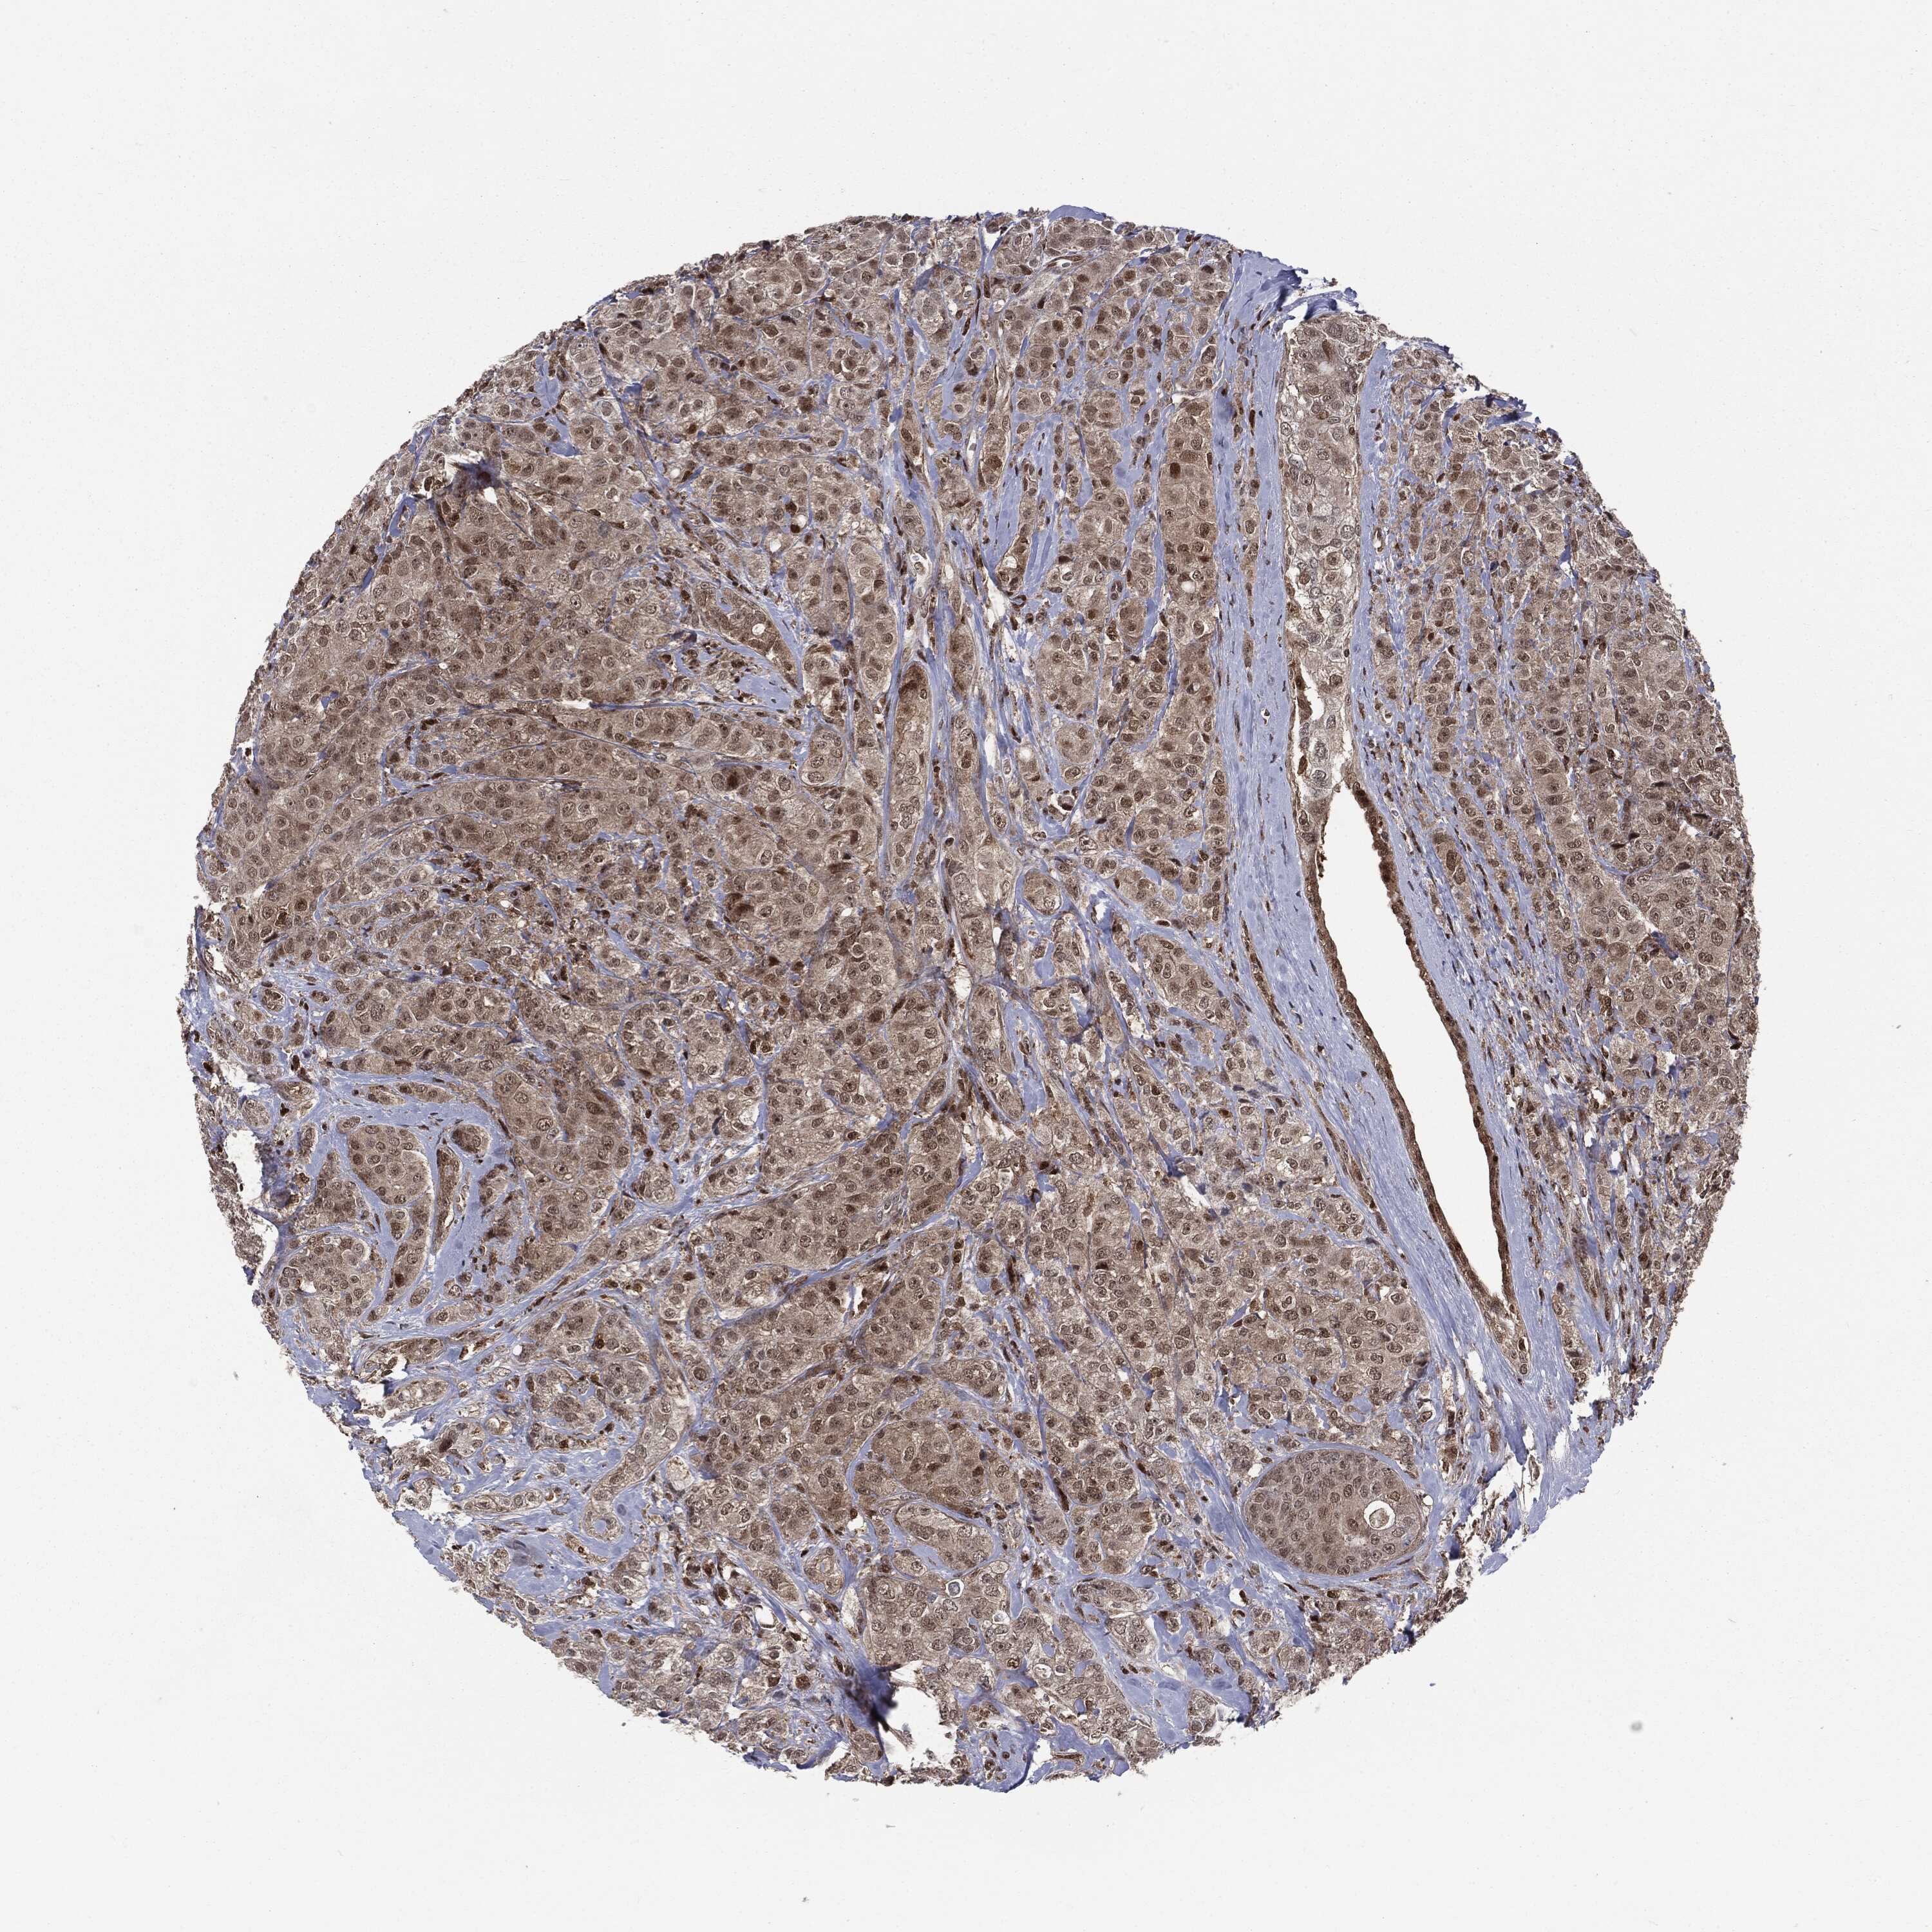

CANCER BREAST CANCER Show tissue menu

BRCA TCGA BRCA VALIDATION PROTEIN EXPRESSION

ANTIBODIES

AND

VALIDATION